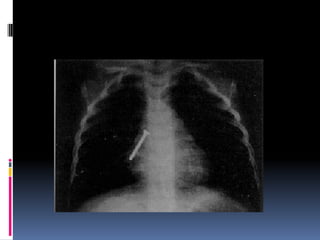

 Estudios Radiológicos.-

 Rx. DeTórax AP. y Oblicuo.

Localización • Inmediatamente pordebajo del músculo cricofaringeo. • Encima de la unión gastroesofágica. • En los relieves que establecen el cayado de la aorta y el bronquio principal izquierdo.

Síntomas  Disfagia ydolor supraesternal - Si el objeto es voluminoso puede producir excesiva y dificultad respiratoria.  Dolor retroesternal con irradiación a la espalda (localización en tercio medio del esófago.  Regurgitación( localización tercio inerior)

Diagnostico  Estudios Radiológicos.- Rx. Simple de Esófago Cervical vista Lateral.  Fluoroscopía de Esófago con mota de algodón  Embebida en bario.  Rx. DeTórax AP. y Oblicuo.  Exploración Endoscópica.